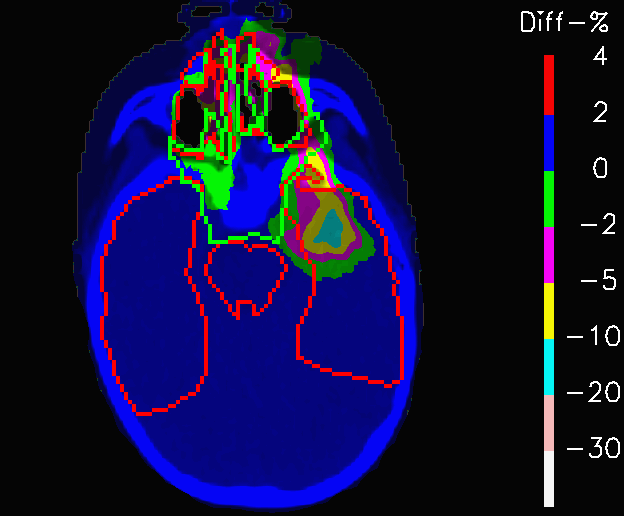

When PLAN-NOM and PLAN-OL are re-computed on the extreme scenario CTs of Fig.4 and the difference between each of these extreme-case plan and the corresponding reference ones are considered, interesting results emerge. Fig.12 shows PLAN-NOM-H and PLAN-OL-H, whereas tables 3 highlights the fact that in both scenarios the target coverage is more remarkably more robust for PLAN-OL than for PLAN-NOM, since 𝐕𝟏𝟎𝟎subscript𝐕100\mathbf{V_{100}} improves by 3.1% in the high-density nose cavities case and by +5.3% in the other one.

Refer to caption

(a) PLAN-NOM-H

(b) PLAN-OL-H

Figure 13: Fields crossing the nasal cavities: difference between the dose distribution re-calculated on the CT with nasal cavities filled with mucus and the one computed on the original CT, for the nominal plan and the one re-computed with OL penalization.